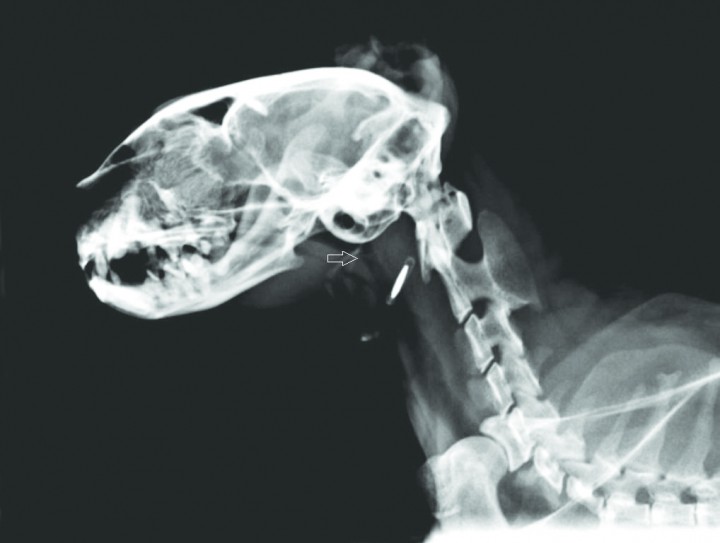

Basándonos en la lista de problemas, se realizan radiografías laterales de la cavidad torácica, cabeza y cuello. En el tórax se observa un leve aumento de tamaño de la silueta cardíaca con un “vertebral heart score” (VHS) de 8 (valores normales: 7,5±0,3) (Fig. 1). En región nasofaríngea se observa una línea de opacidad tejido blando dorsal al paladar blando y una probable elongación del paladar (Fig. 2). Se realiza también un perfil básico que incluye hematología y bioquímica séricas, estando todos los valores en rango normal. Se efectúan, además, tests serológicos para leucemia (FeLV) e inmunodeficiencia (FIV) con resultado negativo.

<p>Radiografía LL de la cabeza en la que se observa una membrana dorsal al paladar (flecha blanca) y una elongación del paladar blando.</p>

Radiografía LL de la cabeza en la que se observa una membrana dorsal al paladar (flecha blanca) y una elongación del paladar blando.